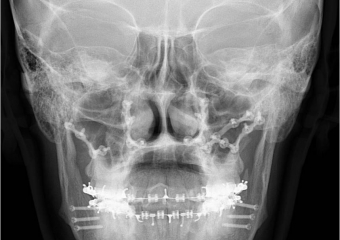

Raio x inicial

Raio x após a cirurgia